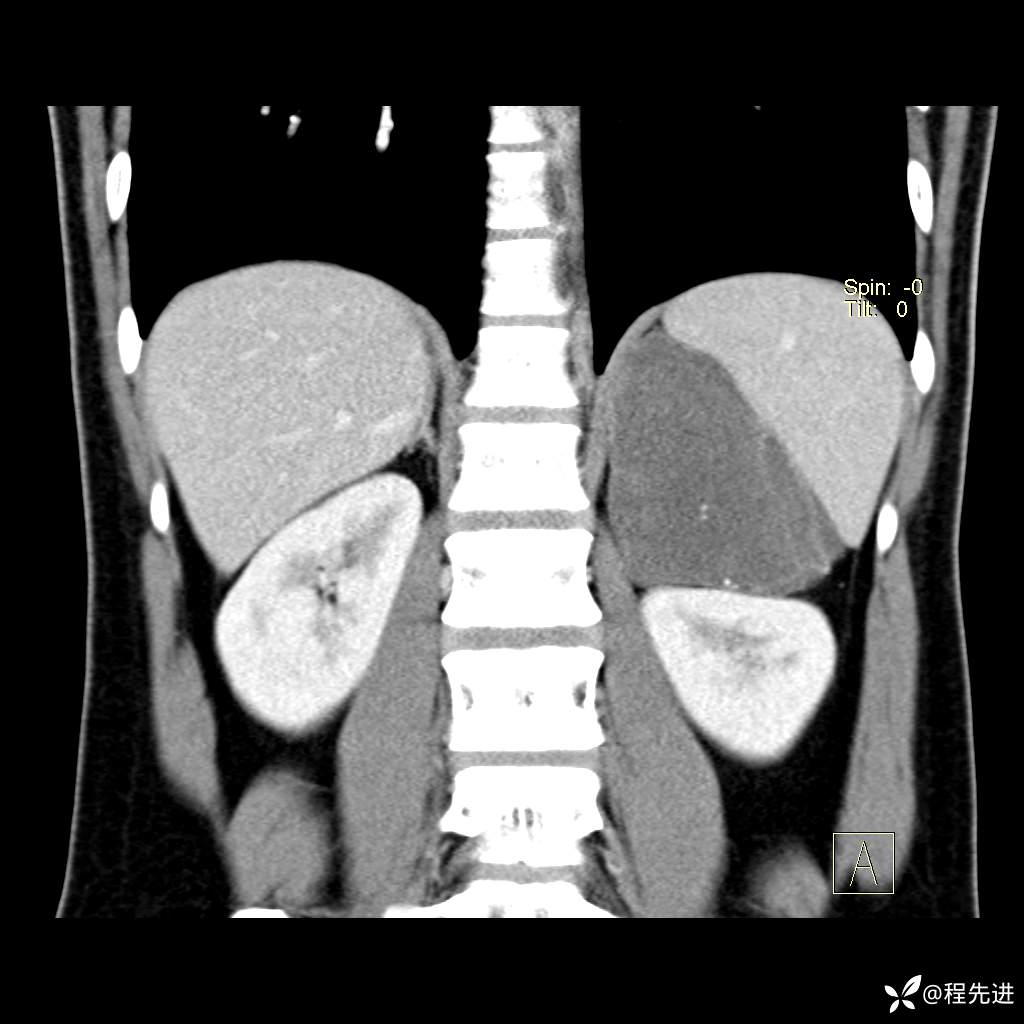

【腹盆】特别精彩病例|体检发现的左侧腹膜后占位期待您的精彩解读

患者年龄:25岁

简要病史:体检发现

CT平扫:(CT值:平扫,27HU,动脉期,27HU,门静脉期,31HU,平衡期,32HU)

冠状位重建: